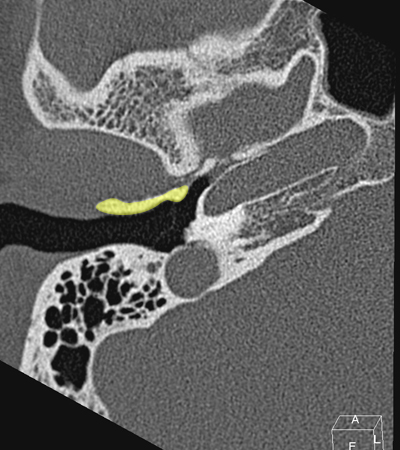

Horizontal petrous carotid Jugula bulb Sigmoid sinus Anterious wall of bony EAC (tympanic bone) Eustachian tube Tympanic membrane Facial nerve (f3), mastoid segment

Radioanatomy of Temporal bone